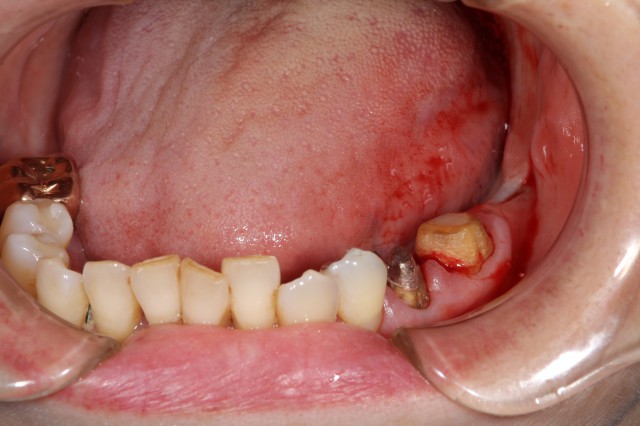

施術後

セラミックによる審美回復の利点は、既存の歯と形や色味を非常に近くあわせられるため仕上がりがとても美しいのが特徴で見た目にはほとんど既存歯と変わらなくなります。今回セラミックによる審美回復された患者様も「これで気にすることなく大きな口をあけられる!」と非常に喜んでおられました。